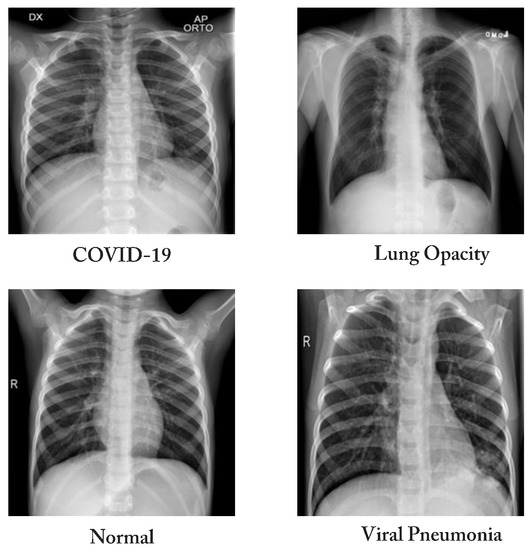

| COVID-19 Radiography dataset [37] | Classes | Number of CXR scans | Sources |

| COVID-19 | 3616 | - BIMCV-COVID19+ dataset [38] (2473 CXR images). | |

| - German medical school [39] (183 CXR images). | |||

| - SIRM, Github, Kaggle, Twitter [40,41,42,43] (560 CXR images). | |||

| - Github source [44] (400 CXR images). | |||

| Lung Opacity | 6012 | - Radiological Society of North America (RSNA) CXR dataset [45] (6012 CXR images). | |

| Normal | 10,192 | - RSNA [45] (8851 CXR images). | |

| - Kaggle CXR Images (pneumonia) database [24] (1341 CXR images). | |||

| Viral Pneumonia | 1345 | - The CXR Images (pneumonia) database [24] (1345 CXR images). | |

| Total number of CXR scans | 21,165 | ||